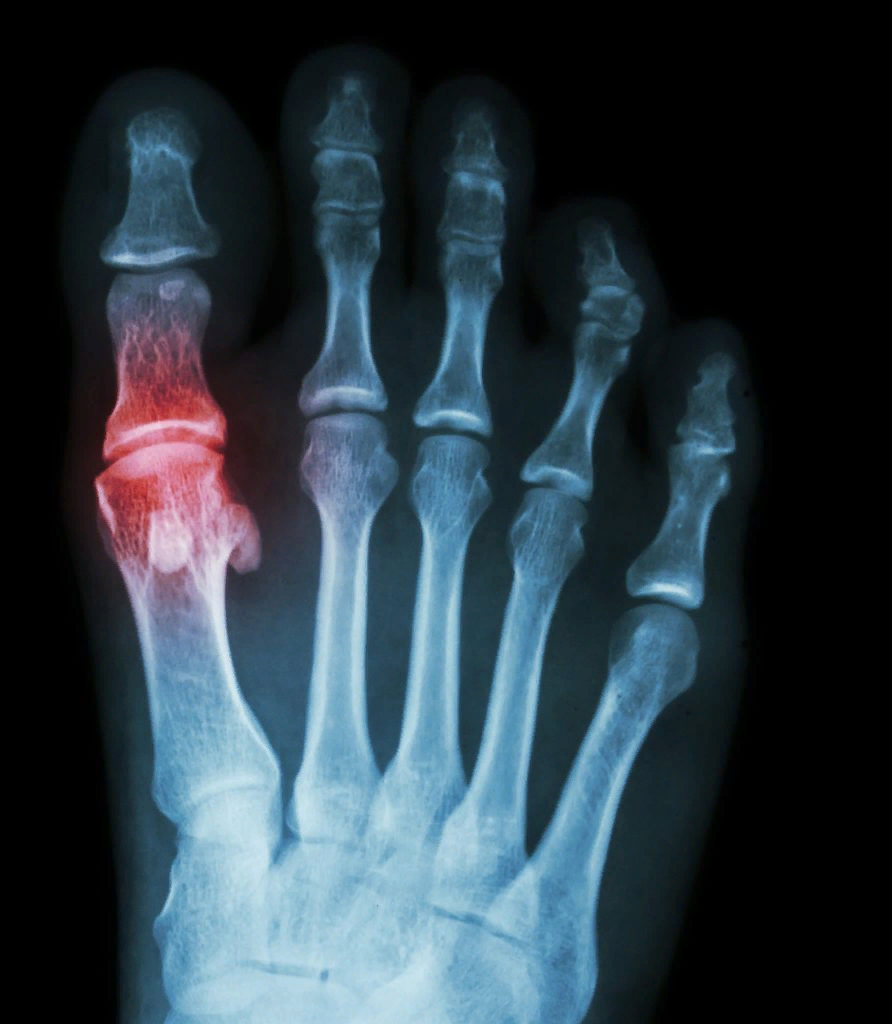

Основание подагры

Заболевание характеризуется отложением мочекислых солей в различных тканях организма. Главное ее проявление - поражение сустава большого пальца стопы. Развитию заболевания способствует ношение тесной и неудобной обуви. Злоупотребление жирами, мясом, помидорами, бобовыми, щавелем, копченостями, солеными продуктами, алкоголем и шоколадом усугубляет протекание болезни.